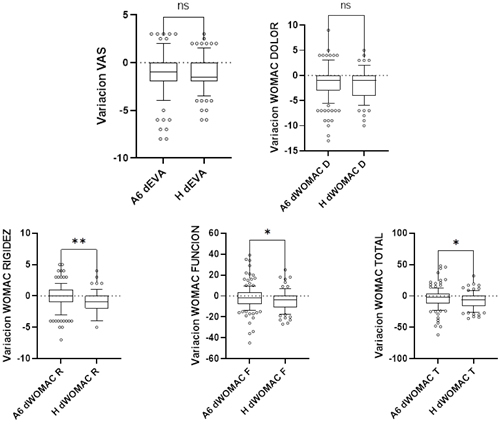

Fig. 2. Cambios de las medias absolutas de las puntuaciones del WOMAC y EVA tras el tratamiento con hialuronato a los seis meses con A y al año con H. Variación absoluta desde los datos basales. A6M: seis meses tras la infiltración con A; H12M: 1 año tras el tratamiento con H. Los diagramas de cajas y bigotes representan la media, los cuartiles superior e inferior y los percentiles 10-90 %, respectivamente. El test de Mann-Whitney fue usado para comparar los grupos con un valor alfa establecido en 0,05 como significativo. Ns: no significativo.

En la Figura 3 se muestra la comparativa de los cambios obtenidos en cada grupo después del tratamiento con AH. En relación con el dolor medido utilizando la escala EVA y con el WOMAC dolor se observa que la reducción se mantiene en ambos grupos, pero sin diferencias estadísticamente significativas (p > 0,05). Por el contrario, los cambios en los índices de WOMAC función, WOMAC rigidez y WOMAC global fueron superiores en el grupo H12M comparado con el grupo A6M (p = 0,040; p = 0,003, p = 0,043, respectivamente).

Fig. 3. Cambios de las medias absolutas de las puntuaciones del WOMAC y EVA tras el tratamiento con hialuronato a los seis meses con A y al año con H. Variación absoluta desde los datos basales. A6M: seis meses tras la infiltración con A; H12M: 1 año tras el tratamiento con H. Los diagramas de cajas y bigotes representan la media, los cuartiles superior e inferior y los percentiles 10-90 % respectivamente. El test de Mann-Whitney fue usado para comparar los grupos con un valor alfa establecido en 0,05 como significativo. Ns: no significativo.